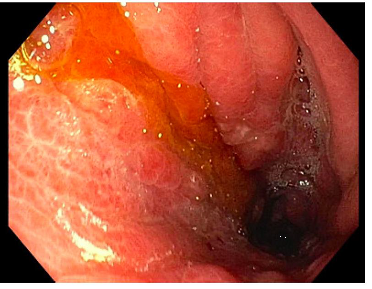

Figure 4 Gastroscopy demonstrating an area of congested, friable and nodular gastric mucosa at the greater curvature.